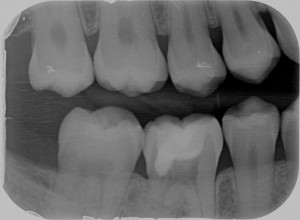

Quando nel 2013 mi è arrivato all’attenzione questo caso

riassorbimento esterno - Radiografia iniziale

Ho riconosciuto lo stesso fenomeno visto nella ragazza infestata da tessuti alieni di cui sopra e mi sono ricordato che all’università si era parlato di riassorbimenti esterni.

Allora ho studiato il fenomeno e ho saputo fare una diagnosi.

Si trattava di un riassorbimento esterno di classe IV.